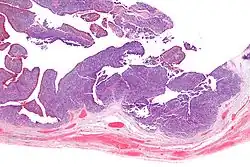

| Micrograph of transitional cell carcinoma of the ovary. H&E stain. |

TCC of the ovary is diagnosed by examination of the tissue by a pathologist. It has a characteristic appearance under the microscope and distinctive pattern of immunostaining.[2]

Low mag.

Very high mag.